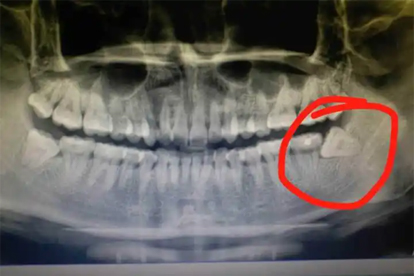

傾斜生長(zhǎng)的智齒會(huì)頂撞第二磨牙,導(dǎo)致鄰牙牙根吸收或齲壞。早期可見(jiàn)鄰牙牙縫增寬,晚期可能出現(xiàn)牙齒松動(dòng)。通過(guò)口腔全景片可明確損傷程度,鄰面齲需采用玻璃離子水門(mén)汀充填,嚴(yán)重者需拔除智齒后修復(fù)鄰牙。

阻生智齒可能誘發(fā)含牙囊腫,導(dǎo)致頜骨膨隆及牙齒移位。X線顯示圓形透射影伴硬化邊。需手術(shù)摘除囊腫并行開(kāi)窗引流,配合甲硝唑片預(yù)防感染。長(zhǎng)期未治療可能引發(fā)病理性骨折。